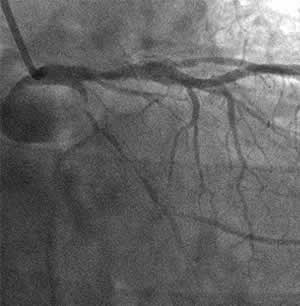

| Diagnosis: AP, SVD

Present Illness: '90.11 PCI for #6 '01.8.21 Stenting for #3 (CTO) '01.9.4 DCA & stenting for LAD |

| Final CAG Findings:'01.9.4 LVG: asynergy (L), EF: 54% CAG: #12 100% (collateral from LAD) |

![]() Control |

Final |

![]() Flexicut M |

![]() Stent 3.5mm/31mm |

I-1 : 6 months follow-up angio